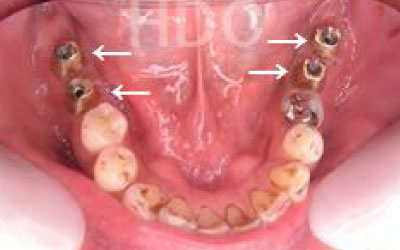

私たちは、インプラントだけでなく

残っている歯も大切にしています。